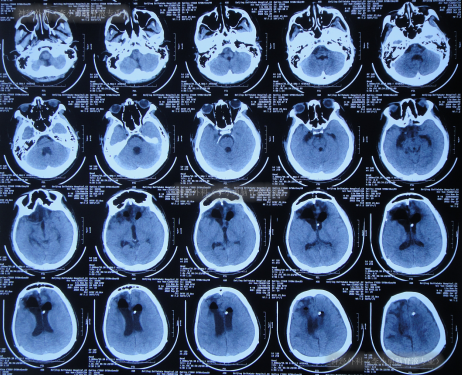

2022年6月9日(颅骨修补术后34天即脑室腹腔分流术后72天)住入李小勇脑脊液专业,入院时:昏迷,呼喊没反应;刺痛后右侧肢体能动,左侧肢体偏瘫;鼻饲流食;小便失禁;头部有手术疤痕(图-16)。

图-16:2022年6月9日入院时

入院时头颅CT示颅骨修补术后,脑分流术后仍脑积水(图-17)。

图-17:2022年6月9日头颅CT

入院后次日即2022年6月10日,拔除了原脑室腹腔分流管+脑室外引流术(图-18)。

图-18:2022年6月10日头颅CT

住院54天即2022年8月2日,头颅CT示脑室进一步缩小(图-25)。

图-25:2022年8月2日头颅CT

住院65天即2022年8月13日,查头颅CT示脑室变小,颅内感染也进一步减轻(图-26)。

图-26:2022年8月13日头颅CT

住院111天即2022年9月28日,病情进一步好转为:意识清楚,言语交流正常,饮食变正常,右侧肢体活动正常,左侧肢体活动差些(图-27);头颅CT示引流术后状态,未见异常(图-28)。

图-27:2022年9月28 日

图-28:2022年9月29日头颅CT

待脑脊液各项化验达标后于2022年10月8日,进行了脑室腹腔分流术(图-29)。

图-29:2022年10月8日头颅CT